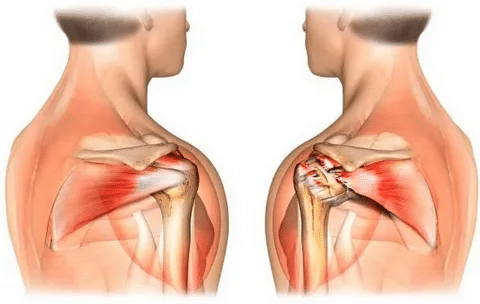

عمل مفصل مصنوعی شانه

درد مفصل شانه زندگی شما را محدود کرده است؟ عمل مفصل مصنوعی شانه ممکن است راه حل باشد. در این مقاله از گروه ارتوپدی سامان، به طور کامل در مورد این جراحی، از جمله مزایا، معایب، روند جراحی، مراقبت های بعد از عمل و موارد دیگر صحبت می کنیم. این مقاله توسط واحد تولید محتوای […]